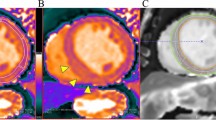

Sixty-year-old man with septal hypertrophic cardiomyopathy and septal fibrosis. a Late gadolinium enhancement (LGE) was found in the interventricular septum (arrow). b Non-contrast-enhanced T1 mapping shows that the native T1 value of the septal region including LGE is 1134 ms, which is more than 1070 ms

Fifty-three-year-old female with progressive signs of left heart failure and infiltrative heart disease suspected at echo underwent MRI for further evaluation. a LGE was found global sub-epicardial enhancement in the anterior, inferior, and interventricular septum (arrow). b Non-contrast-enhanced T1 mapping shows that the native T1 value of the septal region including LGE is 1140 ms

66 Y male with history of coronary heart disease referred for myocardial viability a) Late gadolinium enhancement (LGE) was found sub-endocardial enhancement of the anterior and inferolateral segments (arrows). b) Non-contrast-enhanced T1 mapping shows that the native T1 value of the corresponding regions including LGE (1100 ms)

16 year old male with dilated cardiomyopathy post myocarditis presented with sudden precordial pain like acute myocardial infarction pain, ECG showed ST segment elevation in inferolateral wall (serum creatinine kinease and T-troponin were elevated) (a) Late gadolinium enhancement (LGE) was found mid wall septal, inferior and inferolateral segments (arrow). (b) Non-contrast-enhanced T1 mapping shows that the native T1 value of the inferolateral segment including LGE is 1125 ms, which is more than 1070 ms )

66 year male with history of coronary heart disease referred for myocardial viability. a Late gadolinium enhancement (LGE) was found sub-endocardial enhancement of the anterior and inferolateral segments (arrows). b Non-contrast-enhanced T1 mapping shows that high native T1 value of the corresponding regions including LGE (1100 ms)

16 year old male with dilated cardiomyopathy post myocarditis presented with sudden precordial pain like acute myocardial infarction pain, ECG showed ST segment elevation in inferolateral wall (serum creatinine kinease and T-troponin were elevated). a Late gadolinium enhancement (LGE) was found mid wall septal, inferior and inferolateral segments (arrow). b Non-contrast-enhanced T1 mapping shows that the native T1 value of the inferior and inferolateral segments including LGE is 1125 ms, which is more than 1070 ms)